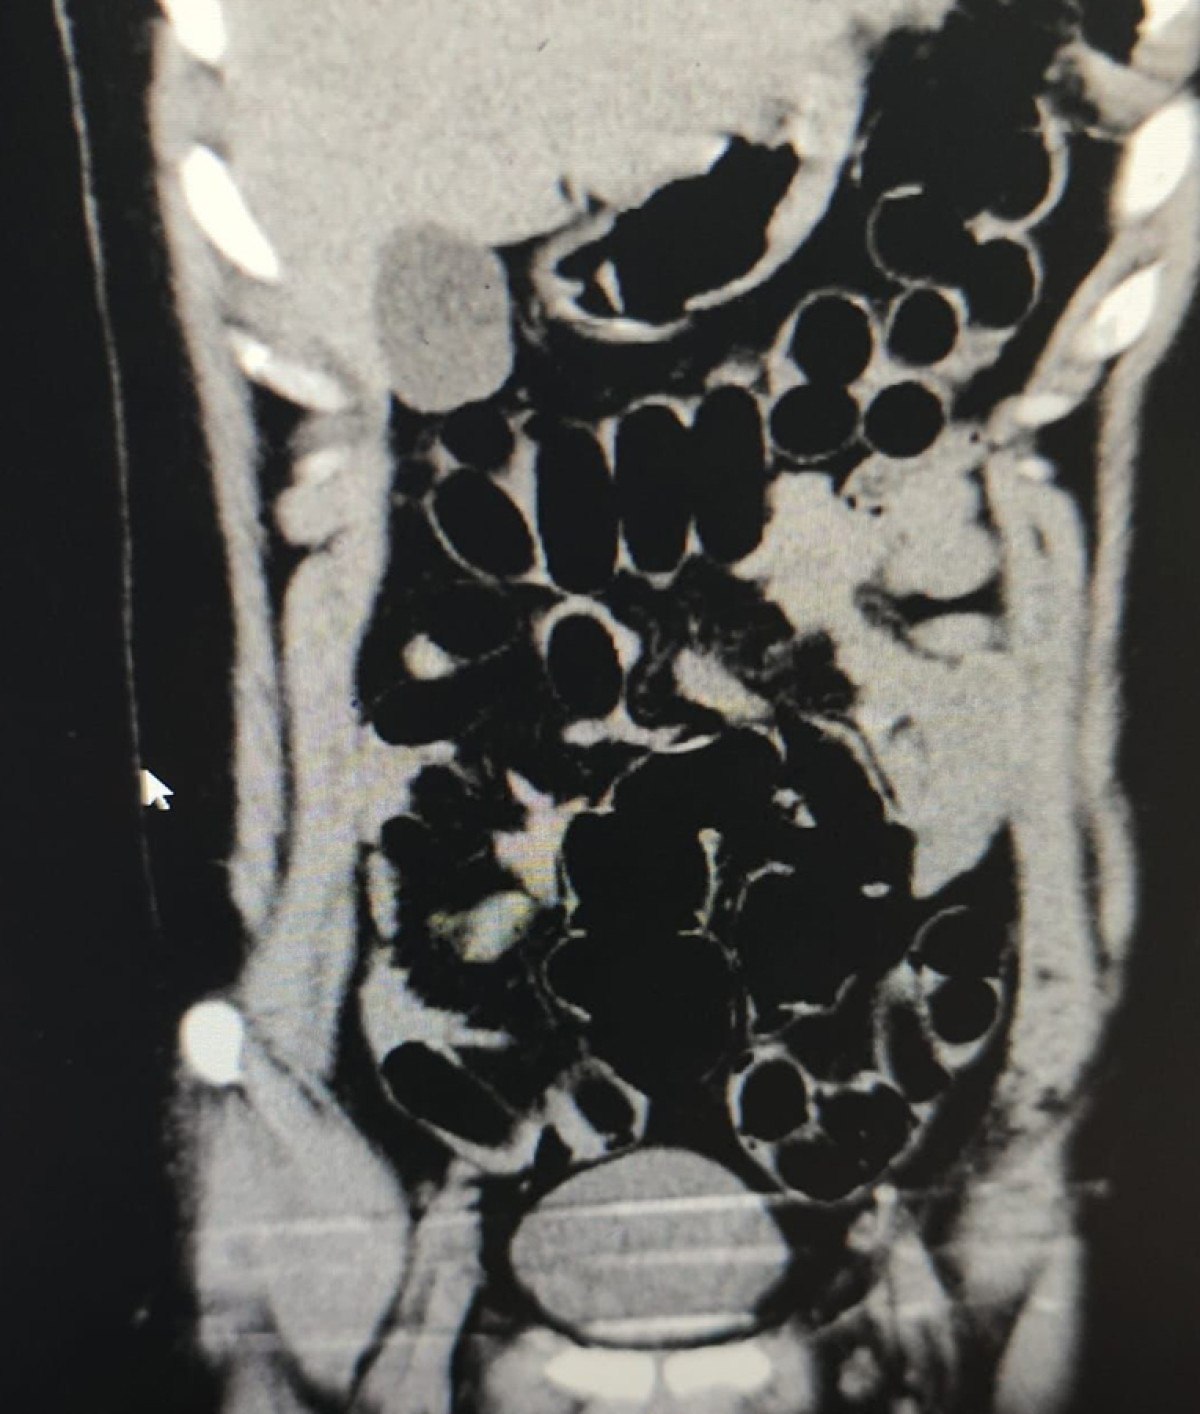

Gözaltına alınarak hastaneye götürülen şüphelinin yapılan iç beden muayenesi ve tomografi görüntülemesinde midesinde uyuşturucu taşıdığı belirlendi.

Midesinden 84 kapsül içinde 842 gram eroin ele geçirilen şüpheli çıkarıldığı hakimlikçe uyuşturucu ve uyarıcı madde ticareti suçundan tutuklandı.